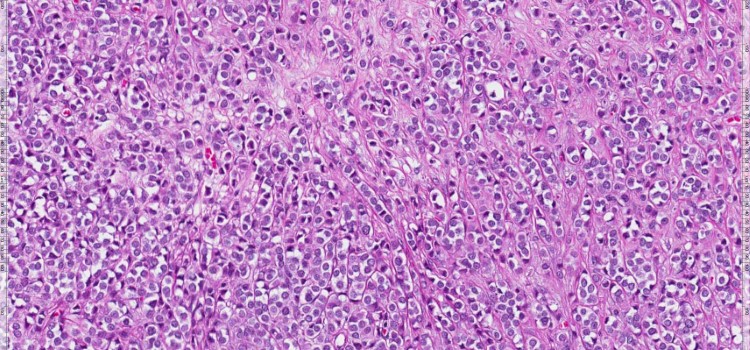

Nuevas claves en la relación de las hormonas de estrés con la hipoxia y la progresión tumoral

08.06.2020

El hallazgo permitiría identificar tumores de mama con un mayor potencial para formar nuevos vasos, crecer y diseminarse